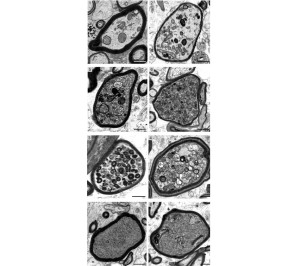

Aufnahmen einzelner Nervenfasern in MS-Hirnbiopsien im Querschnitt (Fotos: uni-leipzig.de) |

Das bisher eigentlich als Schutzschicht der Nervenfasern (Axone) angesehene Myelin kann deren Überleben sogar gefährden. Das haben Forscher der Universität Leipzig im Zuge der Untersuchung von Multiple-Sklerose-Patienten (MS) herausgefunden. Details sind in "Nature Neuroscience" nachzulesen.

Ein Risiko für die Axone besteht zum Beispiel dann, wenn Myelinscheiden durch Immunzellen angegriffen wurden, aber weiterhin die Axone umhüllen und damit von der Außenwelt isolieren. Oligodendrozyten sind nämlich nicht nur für die Bildung des Myelins zuständig. Sie leisten auch wichtige Unterstützungsfunktionen für den Energiestoffwechsel der Axone.

Insbesondere myelinisierte Axone sind stark von metabolischer Unterstützung abhängig, da sie kaum eigenen Zugang zu Nährstoffen haben. Für die Unterstützung myelinisierter Axone durch eine Myelinscheide hindurch ist es erforderlich, dass die Architektur des Myelins intakt ist, einschließlich der engen Kommunikationskanäle zwischen Oligodendrozyten und Axonen.

"Wenn Oligodendrozyten einer akuten entzündlichen Umgebung ausgesetzt sind, könnten sie ihre unterstützende Funktion für die Nervenfasern verlieren und das Myelin wird zu einer Bedrohung für das Überleben der Nervenfasern", so der auch an der Studie beteiligte Forscher Klaus-Armin Nave vom Max-Planck-Institut für multidisziplinäre Naturwissenschaften.